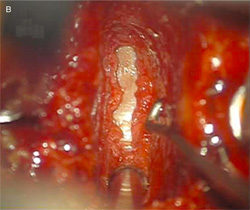

Fig. 3 Fine-cut CT scan (A) demonstrating

fusion of a two-level graft with plating at 3

months post-operatively with pain-free range

of motion, and the day-1 postoperatively

corresponding neutral sagittal and

antero-posterior X-rays (B).

Fig. 4 X-ray of two-level polyetheretherketone (PEEK) cage fusion

without plating 6 months postoperatively demonstrating solid union

posterior and through the PEEK cage implants.